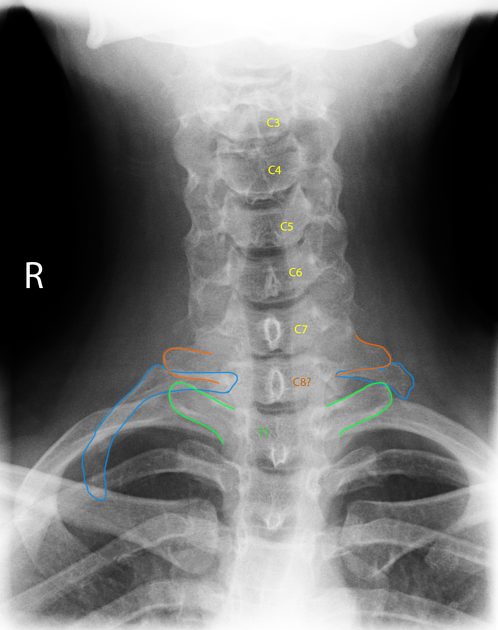

X-ray (neck/chest): can identify bony variants such as cervical ribs or prominent first rib anatomy, and help exclude other bony pathology.

Cervical ribs: important clue, not a diagnosis

Cervical ribs (an extra rib arising from the seventh cervical vertebra) can narrow the space for nerves and vessels and may increase the risk of compression, particularly for arterial TOS. However, the presence of a cervical rib does not confirm TOS. Many people with cervical ribs have no symptoms, and many patients with TOS symptoms have no cervical rib. In practice, a cervical rib is best viewed as a “risk factor” or anatomical variant that must be interpreted alongside symptoms, examination, and appropriate vascular assessment if indicated.